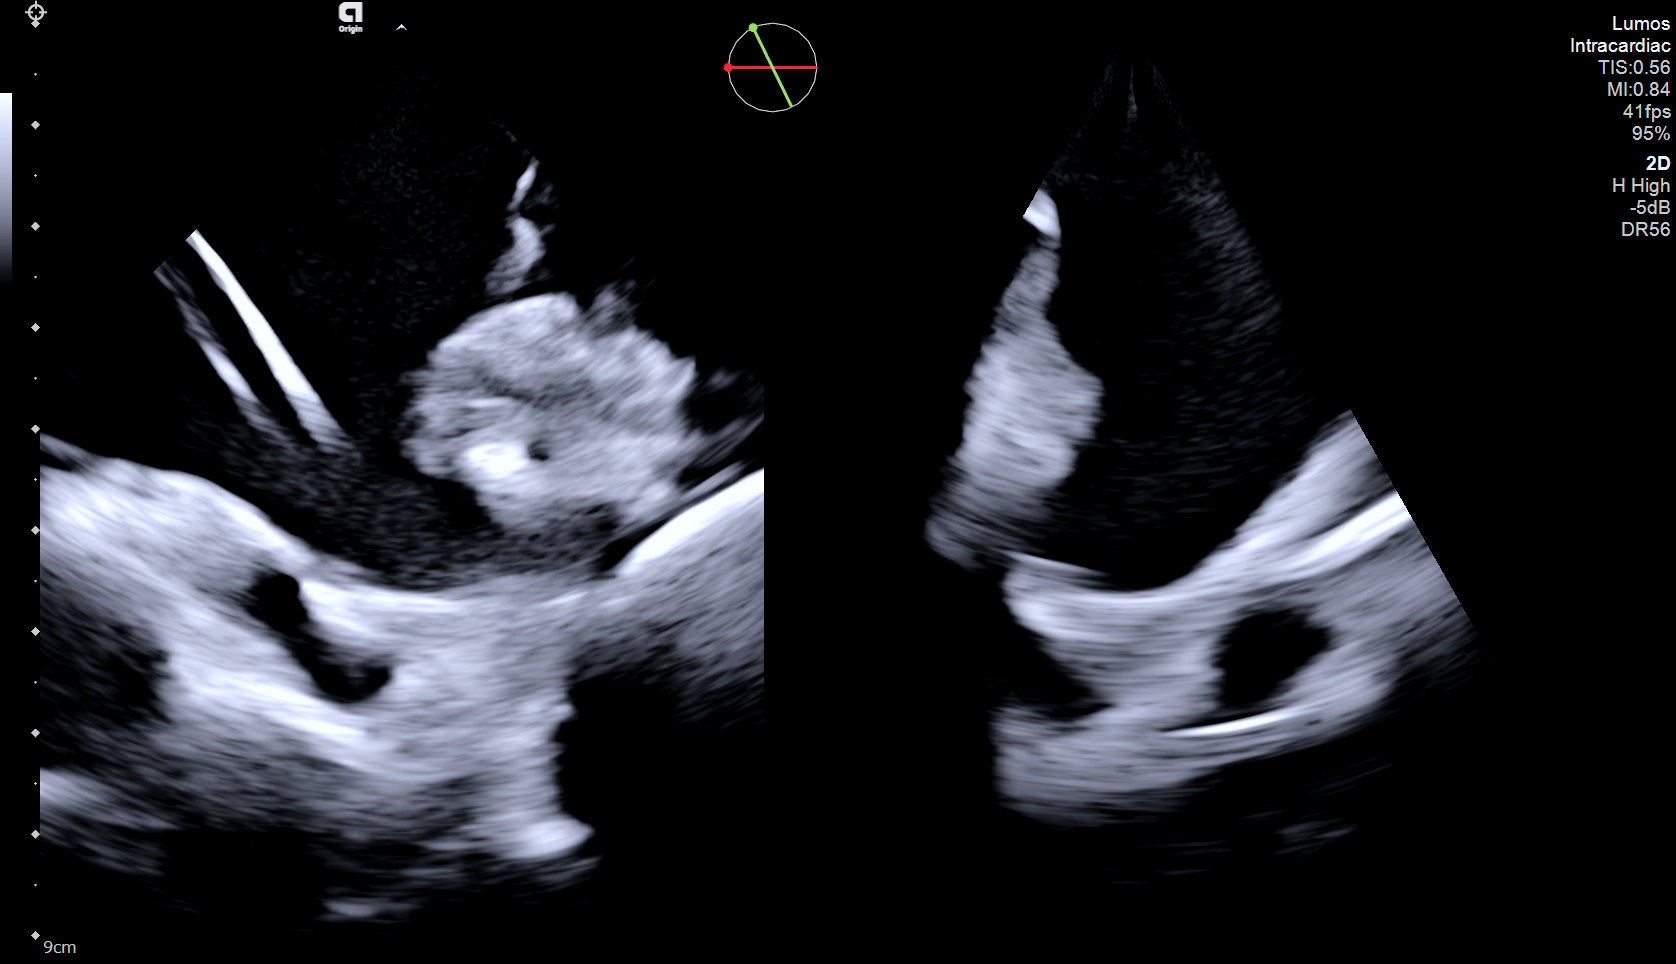

In this case, an elderly female with persistent atrial fibrillation and elevated stroke risk presented for left atrial appendage occlusion (LAAO) evaluation. Due to geographic and logistical challenges in accessing TEE under sedation, the care team opted for a 4D ICE-guided (AcuNav Lumos, Siemens Healthineers) LAAO procedure performed with conscious sedation. Multiplanar reconstructions (MPRs) from 4D ICE were used to assess the LAA’s landing zone dimensions, enabling precise device sizing (Figure 1).